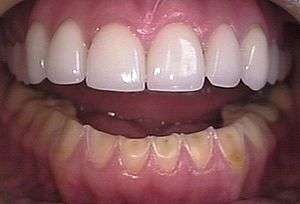

Loss of enamel from the inside of the upper front teeth as a result of bulimia | |

- Perimolysis, or severe dental erosion of tooth enamel[17]

Related disorders